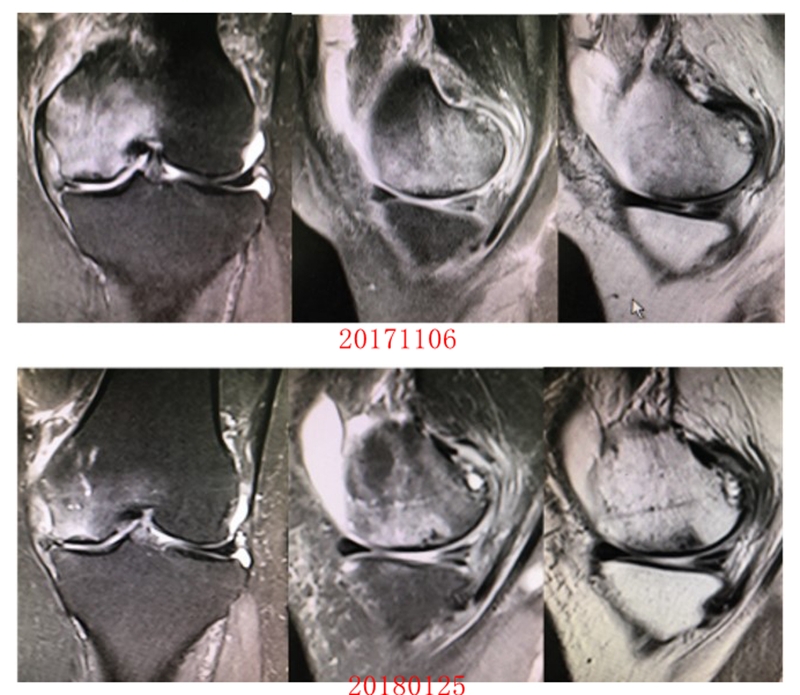

病例2:女,69岁,主诉左膝关节内侧疼痛1月余。2017年11月X光见右膝股骨髁负重区的软骨下区域出现了椭圆形透亮影,MR检查见股骨内侧髁骨坏死,合并内侧半月板外突和后角层裂,半月板相对突出百分比(RPE)25.32%,矢状位病变区域前后径为23.96mm,关节线会聚角6°。

予克氏针钻减压,消炎止痛药物口服、静滴唑来膦酸钠注射液,避免负重6周,后改部分负重至3个月,患者依从性差。2018年1月复查MR见骨髓水肿少许吸收,坏死区扩大,半月板相对突出百分比(RPE)33.53%,矢状位病变区域前后径为26.89mm,患者仍有膝关节疼痛症状,建议行手术治疗,患者拒绝手术后失访。